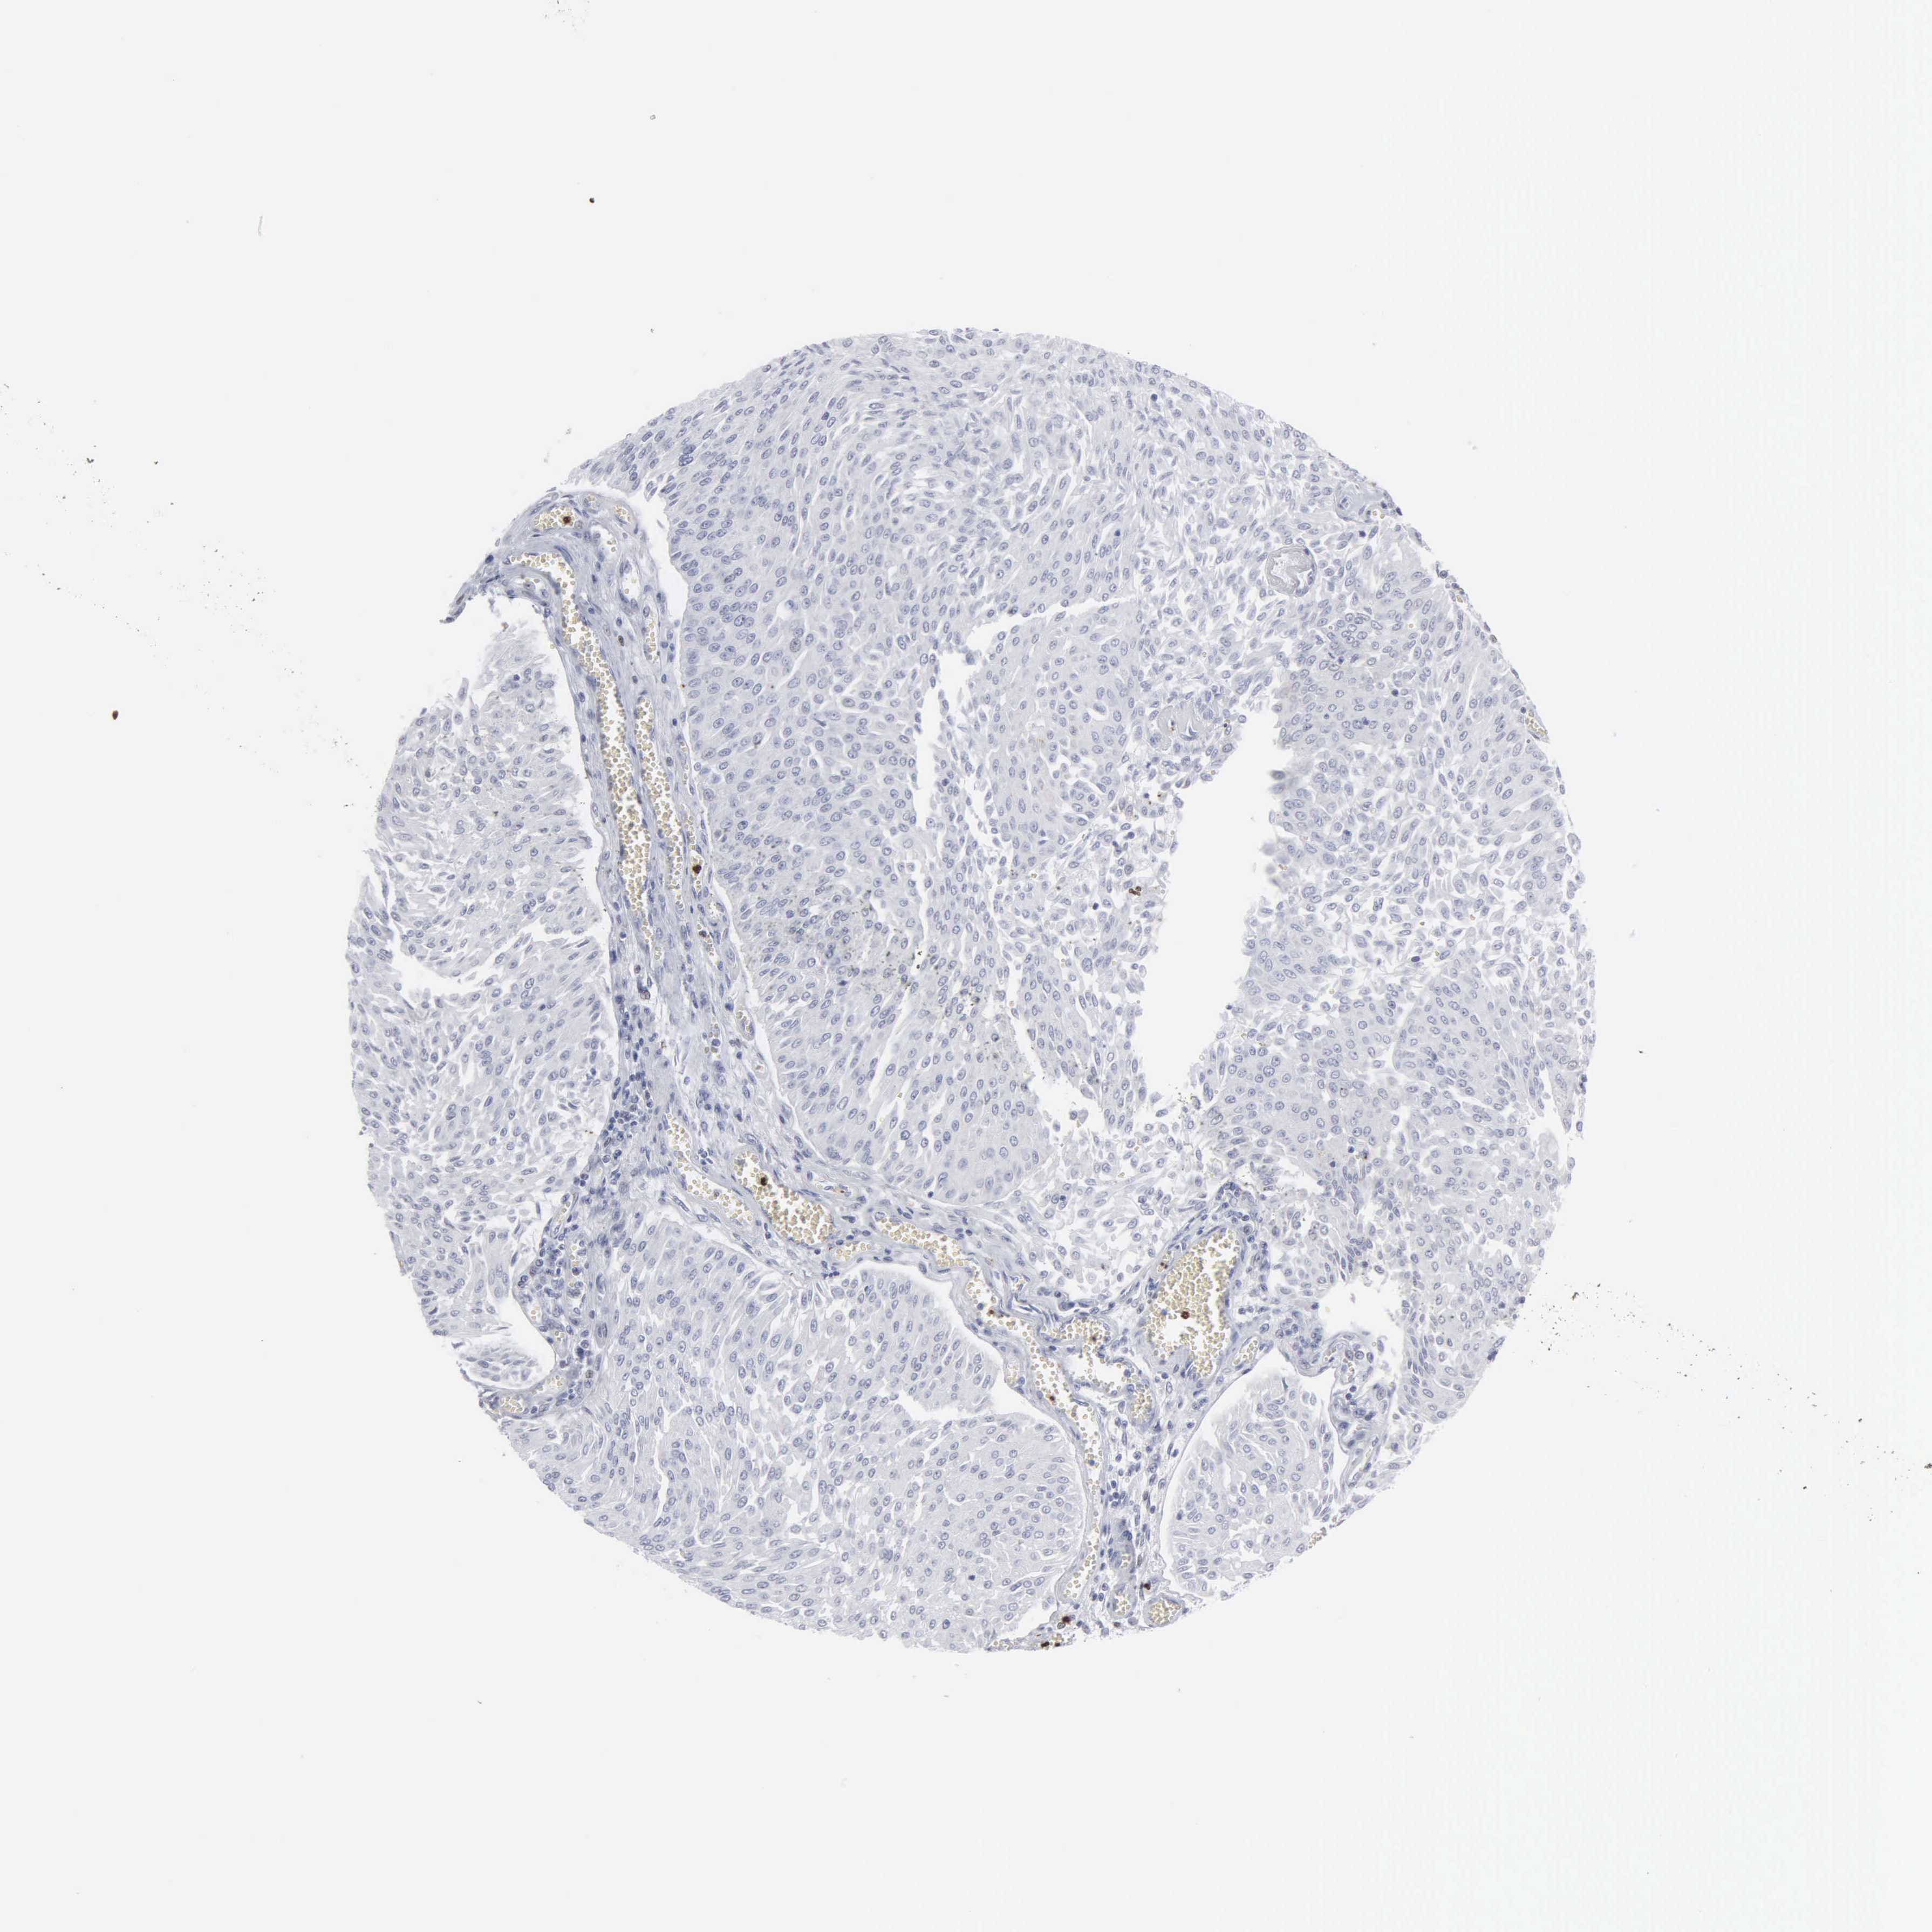

UROTHELIAL CANCER - Protein expressioni

A mouse-over function shows sample information and annotation data. Click on an image to view it in a full screen mode. Samples can be filtered based on level of antibody staining by selecting one or several of the following categories: high, medium, low and not detected. The assay and annotation is described here.

Note that samples used for immunohistochemistry by the Human Protein Atlas do not correspond to samples in the TCGA dataset.

Antibody stainingi

Antibody staining in the annotated cell types in the current human tissue is reported as not detected, low, medium, or high, based on conventional immunohistochemistry profiling in selected tissues. This score is based on the combination of the staining intensity and fraction of stained cells.

Each image is clickable and will lead to virtual microscopy that enables deeper exploration of all samples and also displays staining intensity scores, fraction scores and subcellular localization as well as patient and tissue information for each sample.

Antibody HPA000727

Staining

High

Medium

Low

Not detected

Intensity

Strong

Moderate

Weak

Negative

Quantity

>75%

75%-25%

<25%

None

Location

Nuclear

Cytoplasmic/membranous

Cytoplasmic/membranous,nuclear

Urothelial carcinoma, High grade

Urothelial carcinoma, Low grade